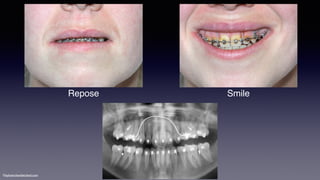

Repose Smile

©sylvainchamberland.com